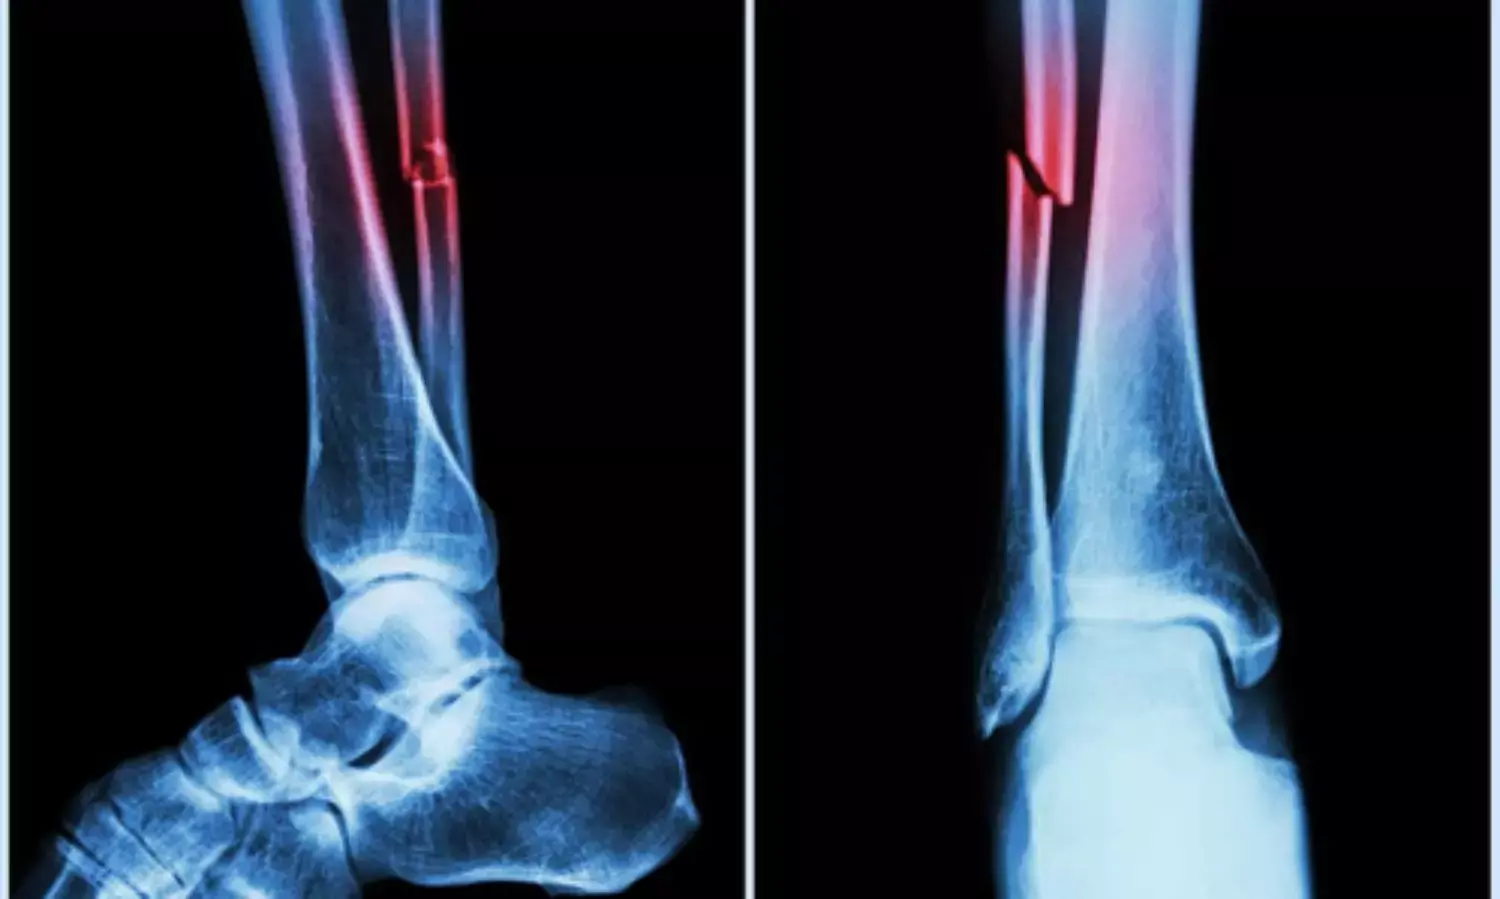

People with T2DM face a well-known paradox in bone biology. Despite having normal or even elevated bone mineral density, the patients experience a higher risk of fractures, particularly in weight-bearing bones such as the hip and femur. GLP-1 RAs have attracted attention because of potential beneficial effects on bone metabolism.